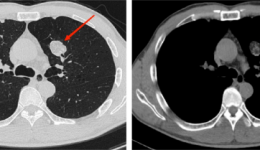

近年来,我国发现肺结节的人群急剧增长,不仅是中老年人群,在青年人群中也常见。这是由于:一则CT检查的普及,二是人们体检筛查意识的提高,故肺结节的检出率逐渐升高,越来越多的人被检出肺结节。很多人看到体检报告提示肺结节,非常焦虑紧张。那...

最近几年,国内越来越多的单位组织职工体检时以低剂量胸部CT取代传统X线胸片,旨在发现早期的肺部病灶,尤其是肺癌。这是非常科学的做法,早期肺癌筛查是降低死亡率的重要措施。那么什么是低剂量CT扫描呢?低剂量CT扫描(Low-dosecomputedtomograph...